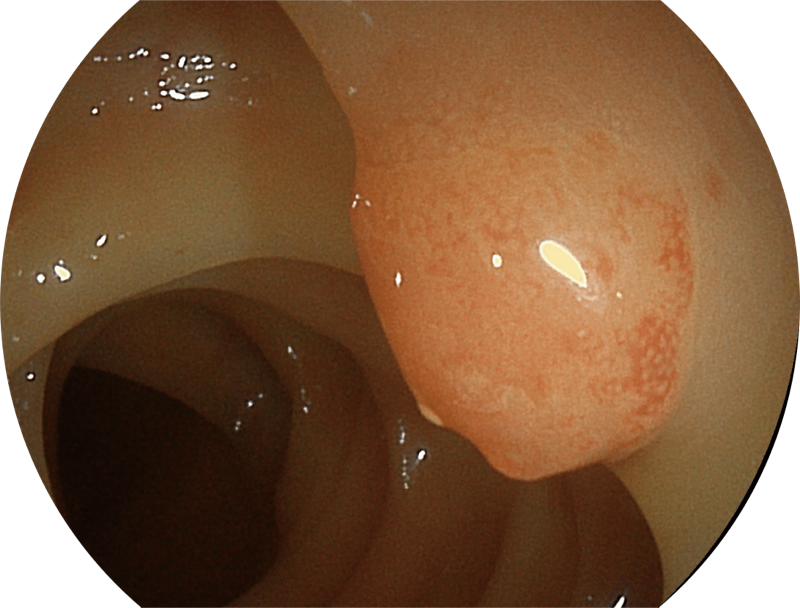

高清画质

百万级像素高清传感器,1080P全高清视频信号输出,图像清晰。